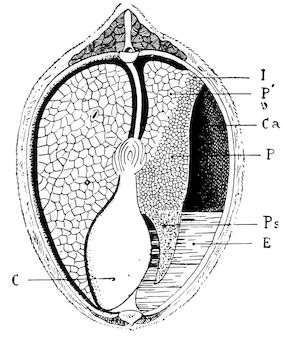

Fig. 9.—C, horn; P, modified skin forming the keratogenous membrane; O, horn core, exhibiting a double sinus.

(2.) The horn-secreting membrane is formed by the skin, which undergoes special development around the base of the horn and comes to resemble that of the coronary band, from which the hoof or claw is secreted. The band is about one-fifth of an inch in breadth. The papillæ of the dermis are specially developed at this point, and the epithelium which they secrete eventually forms the horn.

The internal surface of the growing horn is adherent to the horn core through the medium of another tissue formed by a specially differentiated periosteum which is continuous with the periosteum covering the frontal bone. It is not a true periosteum, but a vascular tissue formed of papillary layers analogous to those of the podophyllous tissue of the ox’s claw or horse’s hoof.

This keratogenous membrane receives a rich vascular supply from the arterial circle formed at the base of the horn core by a division of the external carotid, the blood conveyed by which is freely distributed to the enlarged papillæ. The great vascularity of these parts 23explains why lesions of the horns are often followed by such profuse bleeding.

(3.) The horn secreted by the papillæ of the horn band (which is analogous to that of the coronary band of the horse) forms a cone varying in its curve in various breeds. Its base is hollow, and contains little depressions holding the papillæ from which the horn is secreted. From its base up to the end of the horn core the walls progressively increase in thickness. From this point it is solid; in a fully-grown horn the bone does not extend more than one-half or two-thirds of the entire length.